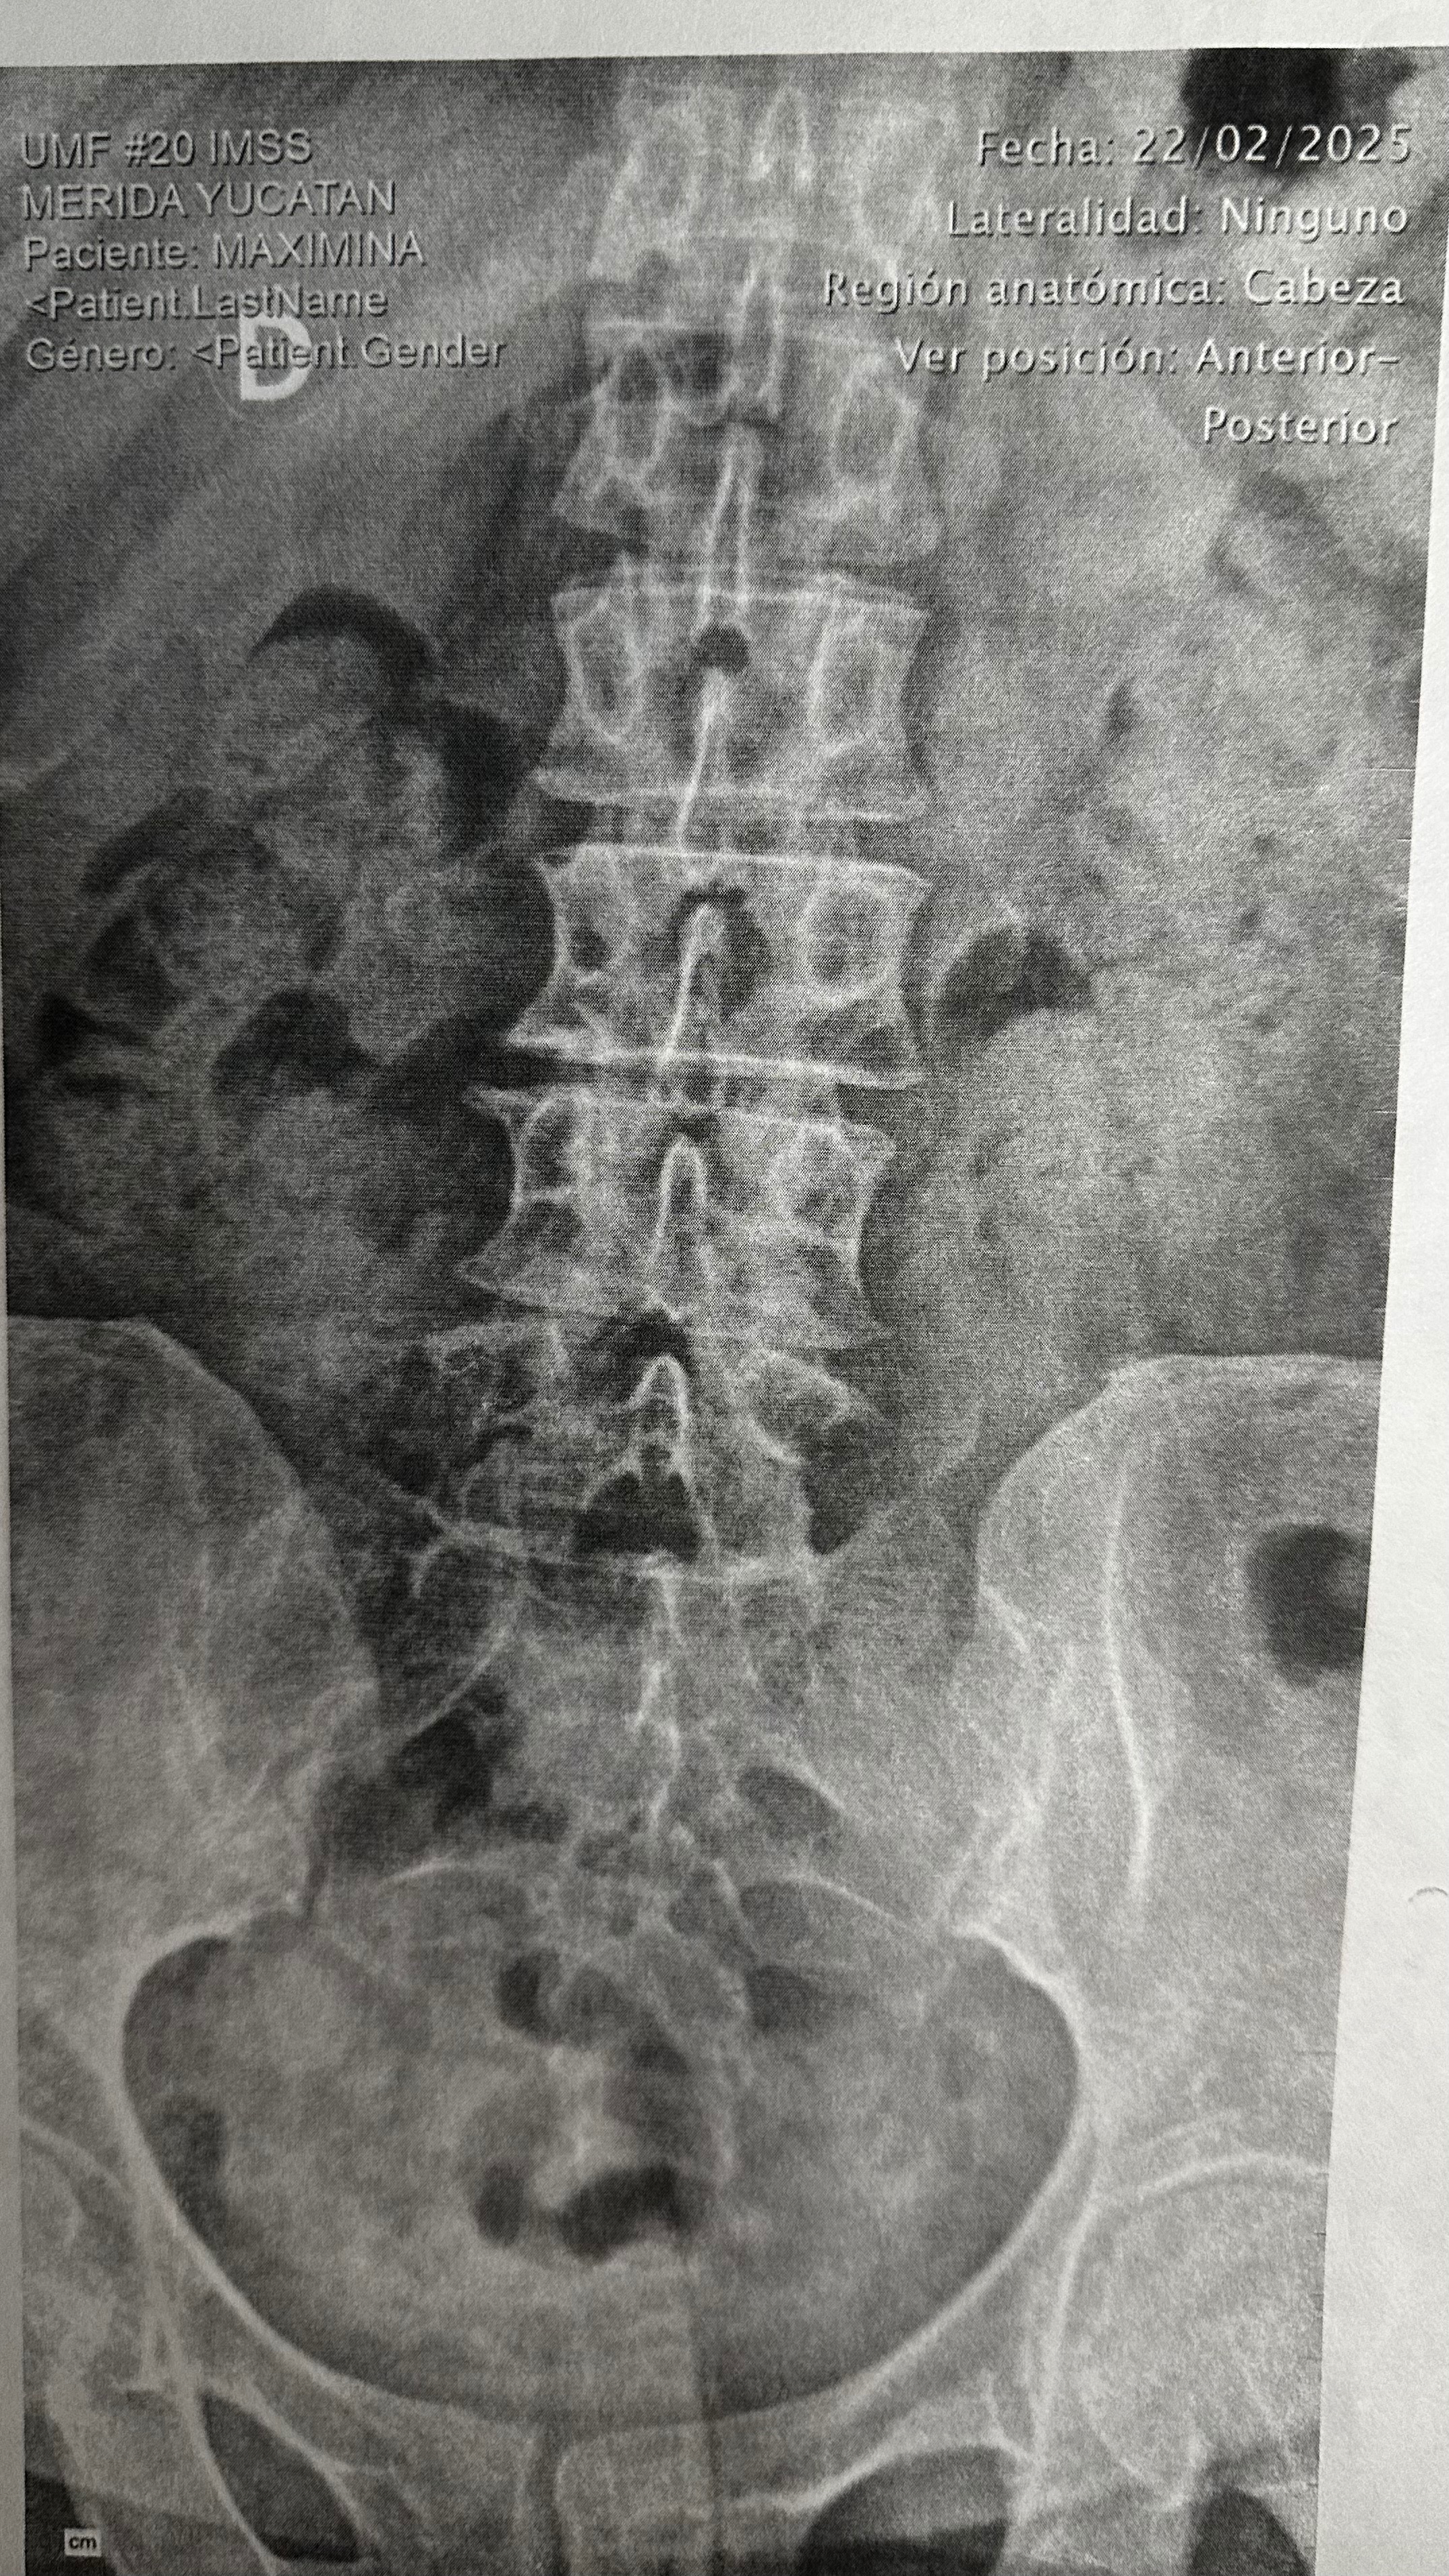

Mi mamá lleva más de 4 años viviendo con un dolor constante en la espalda baja debido a hernias . Este dolor le ha impedido caminar con normalidad; cuando lo intenta, siente un entumecimiento en la entrepierna y debe detenerse, dice que siente como hormigueo. Cada paso se ha convertido como en un reto y esto afecta su vida diaria. Ya la habían tratado para este dolor y solo la mandaban a terapia, le recomendaron hacer ejercicio antes de saber que era hernia y lo hacía aunque le doliera para que mejorara, y fue hasta este año que se logró hacer una resonancia magnética con el sector público y pudimos ver que era la hernia discal, que desafortunadamente está muy avanzado, al punto que hoy en día apenas y puede dar unos pasos y después se le entume sus piernas y pierde fuerza en ellas y ya no puede continuar caminando

Ella siempre ha sido una mujer activa, vendía comida los fines de semana, una barbaboca muy rica por cierto! pero hoy ya no puede realizar muchas de las actividades que antes hacía. Además, este año fue diagnosticada con diabetes, (hace 3 meses) lo cual vuelve su situación aún más delicada , el médico en el sector público que la atiende, le dijo también que si se opera tiene un 75% de posibilidad de salir bien y no tiene empatía para explicar las cosas, que puede no volver a caminar o incluso morir mientras le ponen la anestesia general, mi mamá llegó asustada con mi papá, y aunque no tenemos los recursos para ingresarla a otro hospital, por ahora estamos en espera de esa solicitud del sector público :/ por qué mi mamá ya no aguanta el dolor y aunque tiene miedo también tiene fe en Dios en que todo saldrá bien

Actualmente está en seguimiento (sector público), el dolor ha ido avanzando cada día más, se entumece la entrepierna, y no puede caminar con fluidez

Por eso estoy recurriendo a esta campaña, les pido de todo corazón que si está en su voluntad de ayudar no importa el monto o aunque sea compartir esta publicación se los agradecería, me encantaría poder ayudarle a recuperar su movilidad a mi mamá y más poder llevarla a un sitio donde puedan tratarla con más empatía y humanidad, y lograr ya hacerle la cirugía que requiere para que vuelva a caminar, nosotros ya tenemos los análisis médicos, y el diagnóstico que hicimos por parte del seguro este año, yo sé que no siempre se puede con la parte económica y aquí existen muchos casos y quizá el mío no sea el más grave, pero es mi mamá, y para mí lo es… :( hoy recurro a ustedes para que con su apoyo y generosidad pueda operarse lo antes posible, les estaré actualizando su estatus y avance médico